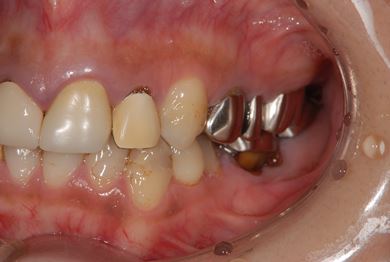

| 性別/年齢 | 女性 / 38歳 | ||||||||||||||||||||||||||||||||

| 主訴 | 奥歯の痛み(虫歯)。銀歯の所だと思います。なるべく痛くない治療がいいです。 | ||||||||||||||||||||||||||||||||

| 治療方針 | セラミック治療にて、審美的回復を行う。 | ||||||||||||||||||||||||||||||||

| 治療内容 | ハイブリッドセラミッククラウン1本(ハイブリッドセラミック用土台1本) | ||||||||||||||||||||||||||||||||

| 総治療費 | 96,600円 | ||||||||||||||||||||||||||||||||

| 治療期間 | 2ヶ月 |